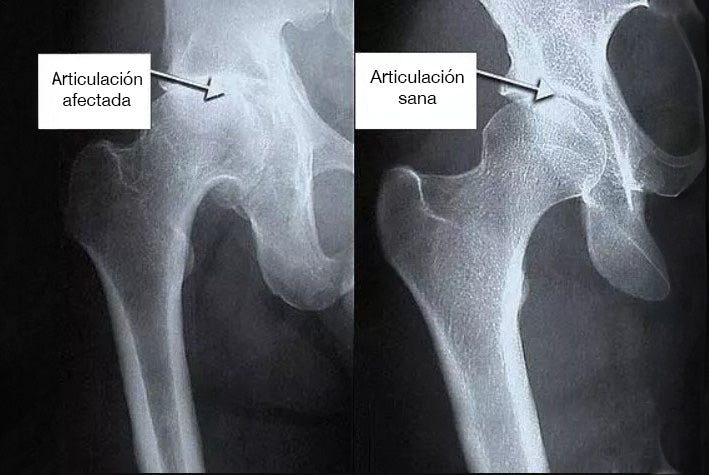

Novedad para las articulaciones y los músculos